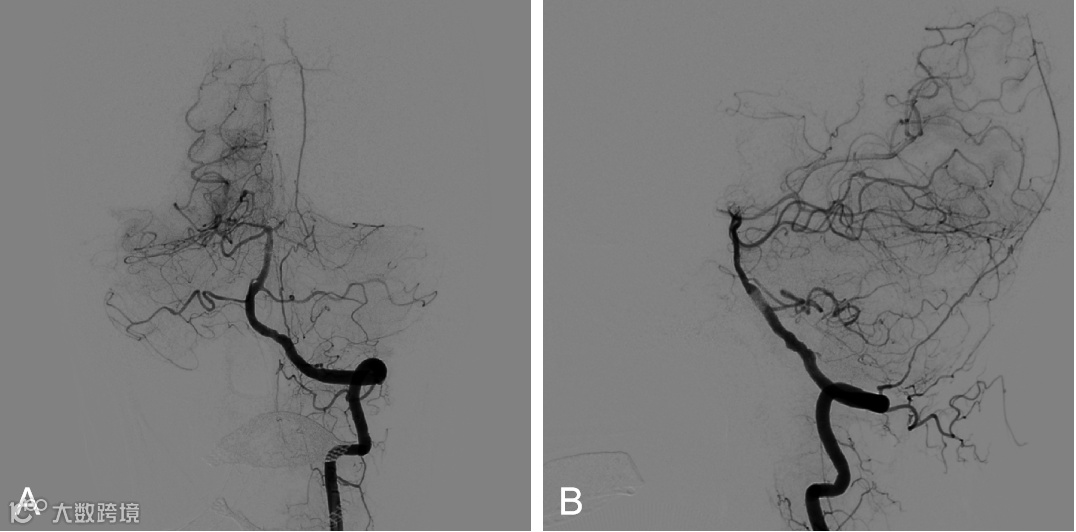

外院DSA示:基底动脉尖动脉瘤(图2 A,B)

图2